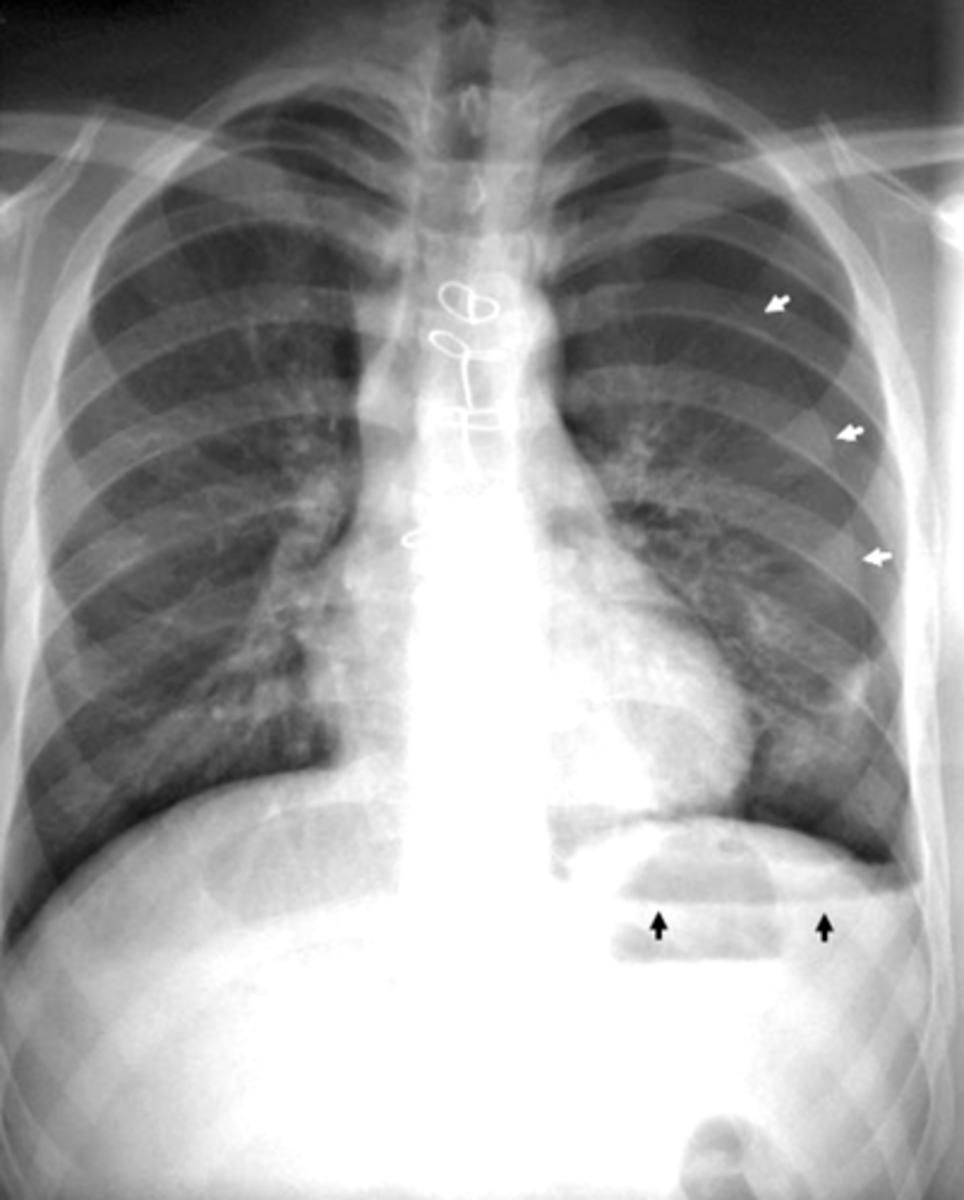

Pneumothorax (caused by stabbing)

visceral pleural line in the left chest (white arrows).

horizontal line along the base of the left hemithorax, which represents an air-fluid level (black arrows), showing that the patient has a hemopneumothorax.

2 key findings in this x-ray and dx